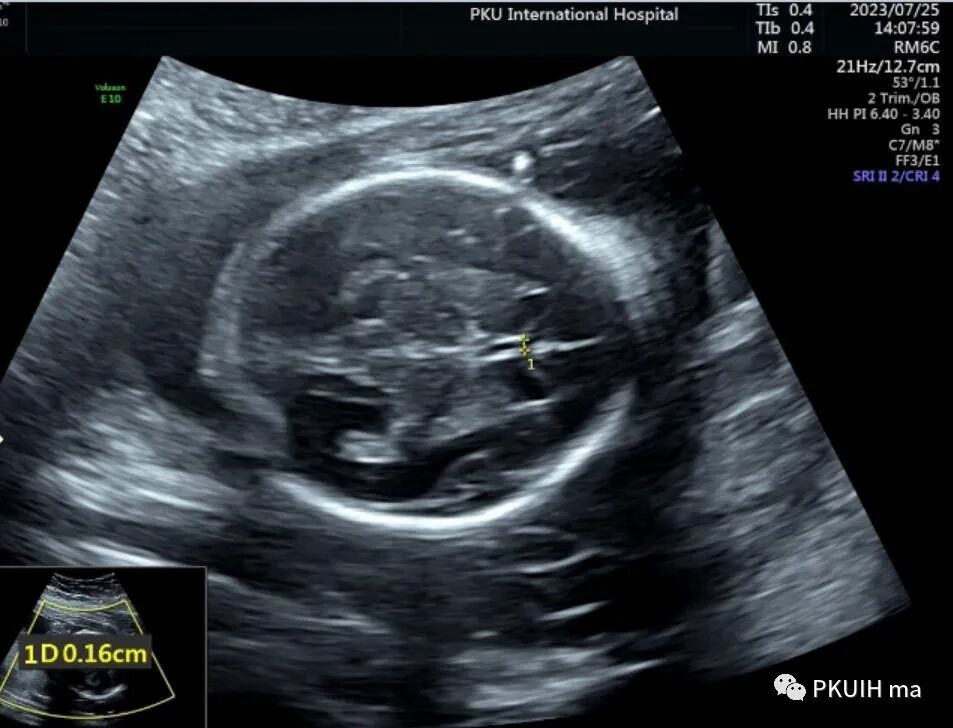

昨天看了一个孕妇,透明隔腔比较细窄,由于胎儿姿势不好和孕妇较胖做了四次也没有很好的完成胎儿神经系统筛查,打算过几天再看。

胎儿透明隔腔比较小(内径约1.6mm),透明隔存在,与侧脑室前角无相通,韦氏腔也比较小只有2.4mm